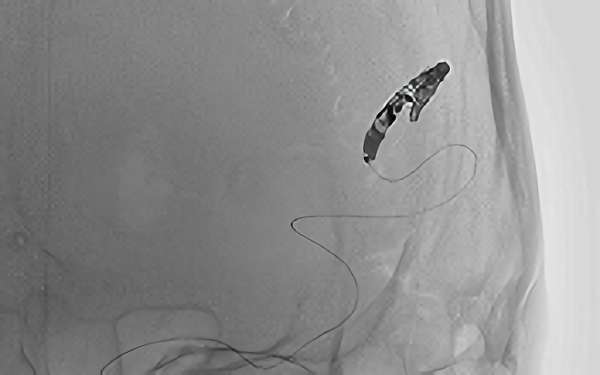

'26年3月

出血性脳動静脈奇形

10代

院内外来

No.1620 手術中